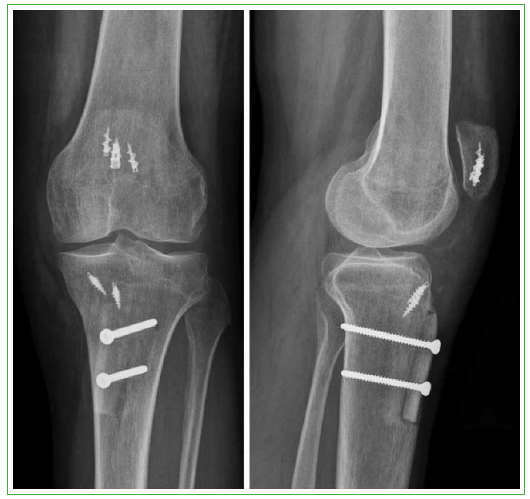

Figura 5.

Radiografías de rodilla, de frente y de perfil, tras la reconstrucción con aloinjerto de aparato extensor.